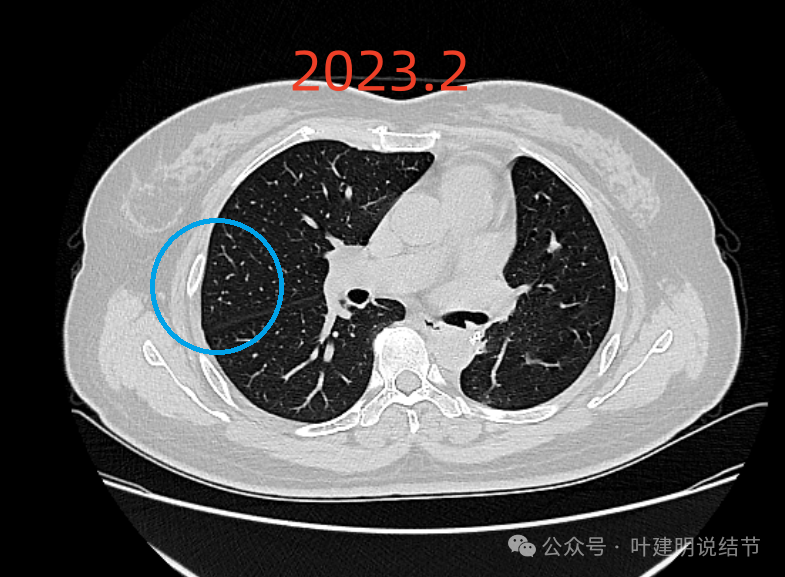

2023年2月时右上叶同一处没有明显病灶。